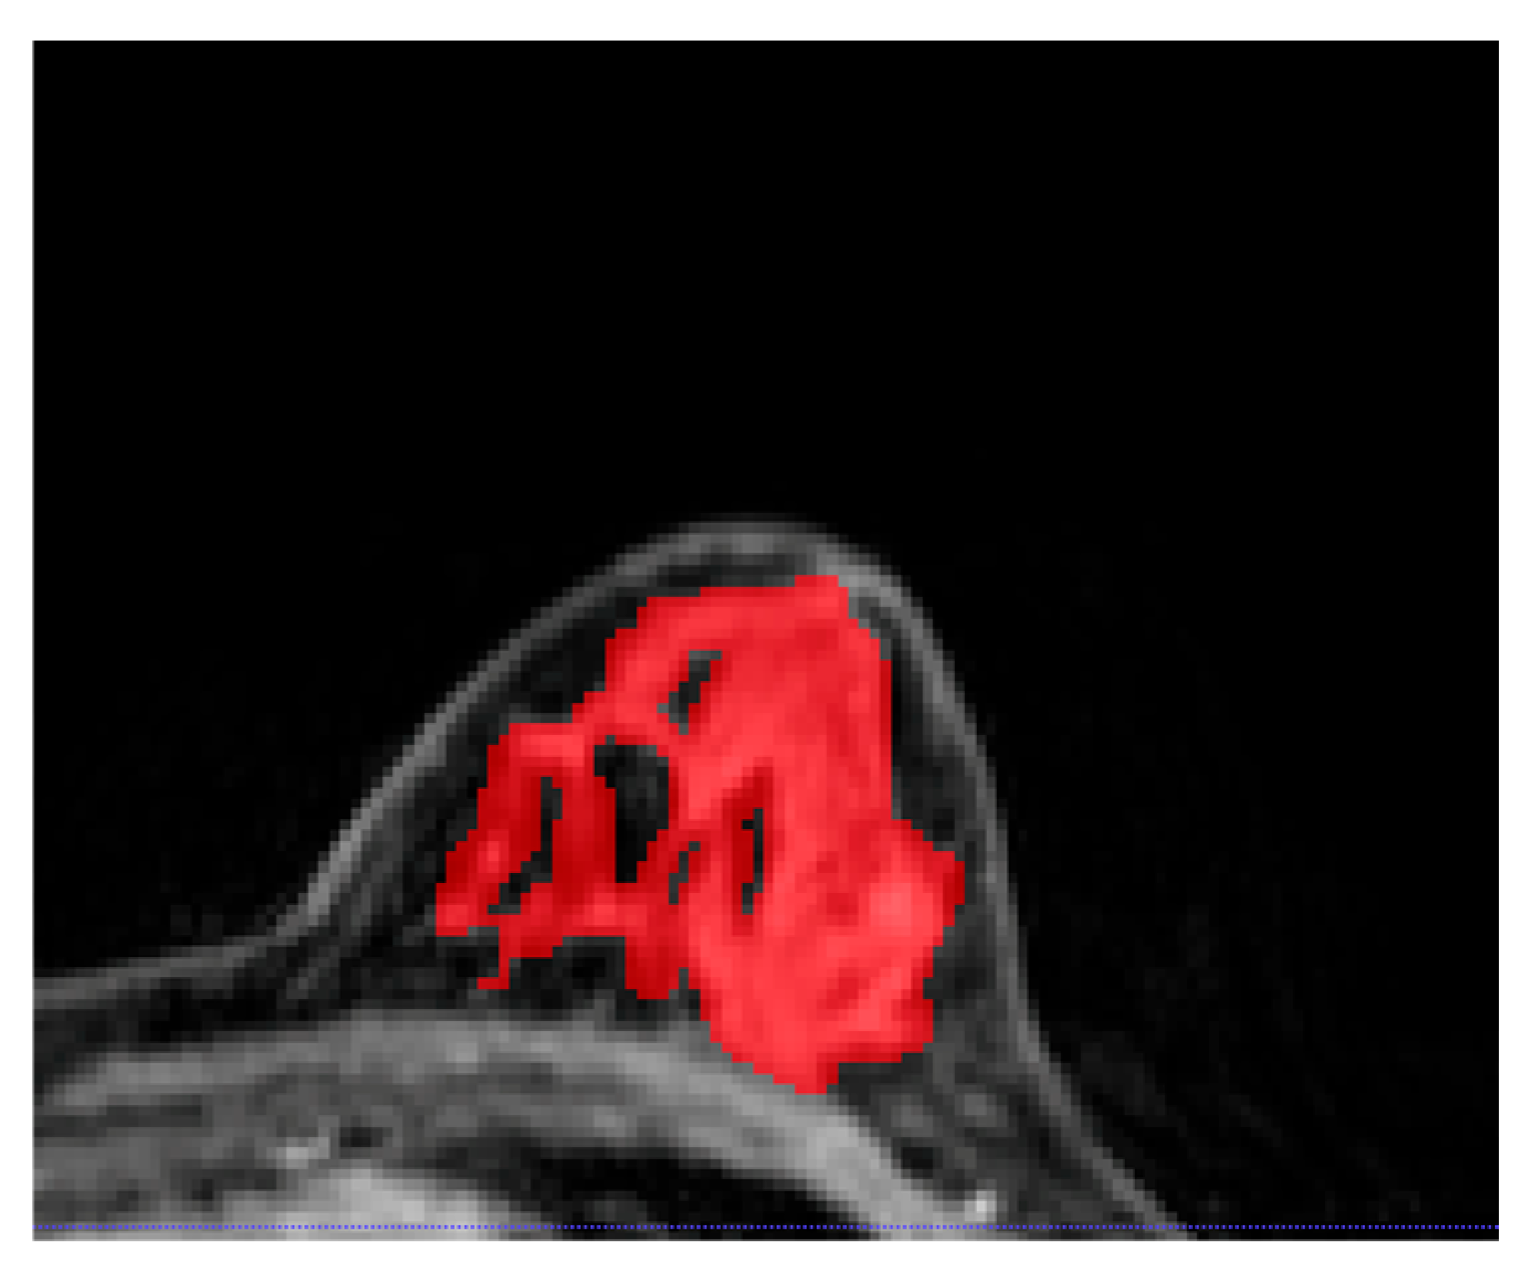

Images from the DCE-MRI T1-weighted fat-saturated first post-contrast sequence were loaded as Digital Imaging and Communications in Medicine (DICOM) files into OsiriX (Pixmeo, Switzerland), an open-source image processing tool [18]. The semi-automated 2D segmentation of FGT of the contralateral unaffected breast was performed as follows: first, thresholding or clustering was performed using ITK-SNAP software (version, 3.6.0) (GNU General Public License, 2004) [19] to include the entire FGT (excluding fatty tissue); subsequently, manual corrections were made by two dedicated breast radiologists (E.O-A. and R.L.G., with 2 and 9 years of experience, respectively) (Figure 1).

Figure 1.

An example of fibroglandular tissue segmentation from the contralateral healthy breast on post-contrast T1-weighted imaging. Interspersed as well as surrounding subcutaneous adipose tissue were excluded from the segmentation.